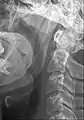

Ossified stylohyoid ligament or elongated styloid process